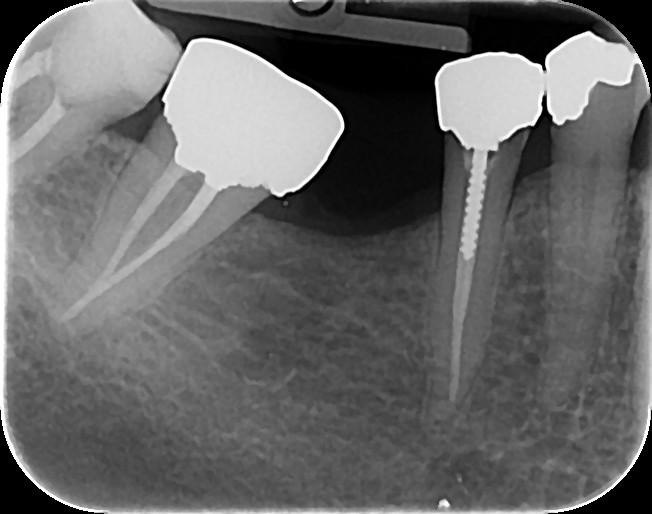

46. Which teeth shows recurrent caries?

47. Which surface(s) shows recurrent caries?

50. Which surface(s) shows recurrent caries?